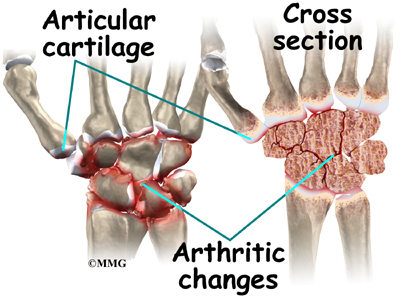

- 손목을 이루는 모든 관절에서 발생할 수 있습니다. 특히 주상골(Scaphoid)와 관련되어서 많이 발생하게 됩니다. 거의 손목의 관절염에서 90%이상이 주상골과 관련되어 있다고는 연구도 있습니다.

- 외상 후에 주상골이 잘 붙지않아 생기는 부정유합이나 무혈성 괴사가 주요 원인일 수 있고, 주상골 주변에 인접한 관절의 손상이 중요한 원인이 됩니다.

- 다른 부위의 퇴행성관절염과같이 수년동안 서서히 심해지고, 손목통증과 관절의 경직과 관절운동범위의 제한이 함께 나타날 수 있습니다.

- 앞서 말했듯 퇴행은 주상골주변에서 가장 많이 발생합니다.

- 보통 처음에는 요골경상골기(Radial styloid)와 주상골의 닿는 부분에서 관절염이 우선 발생되고 이 후 주변 관절로 침범하게 됩니다.